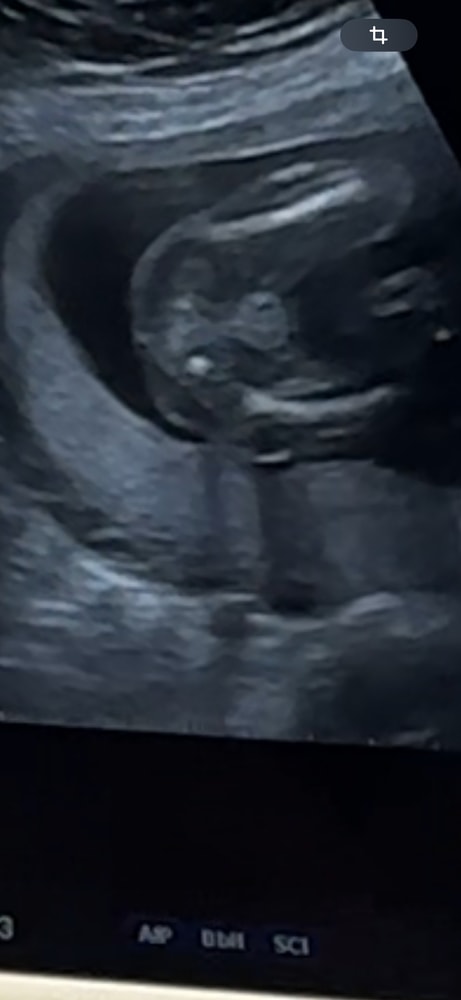

Мальчик ?

Конечно мальчик, все прелести мужские на фото😁

Вроде бы, если это то о чем мы думаем